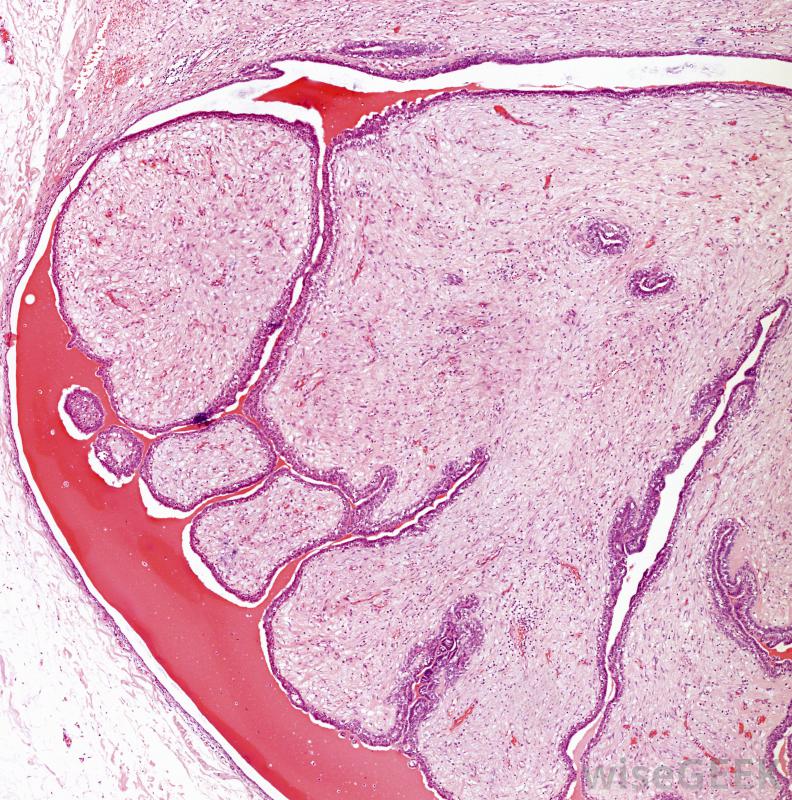

一旦发现乳腺纤维腺瘤,将其留在乳腺通常是安全的,但要定期检查其大小是否增大大多数纤维腺瘤大致呈球形,包含腺体和纤维组织。触诊时,纤维腺瘤感觉有点像大理石,由于肿瘤没有附着,它会在乳房内自由移动。大多数出现在乳房光环后面,左乳房比右乳房更常见,估计每10个女性中就有一个会在某个时候发现乳腺纤维腺瘤,大约百分之一的女性患有多发性纤维腺瘤乳腺x线摄影通常用来确定肿块是纤维腺瘤。一些研究表明,纤维腺瘤的形成可能与雌激素有关使用激素节育的青少年似乎更容易患乳腺癌,这支持了这一理论。然而,纤维腺瘤形成的确切原因尚不清楚。研究表明,患有纤维腺瘤的女性更容易在晚年患上乳腺癌,这导致一些人错误地认为纤维腺瘤会导致乳腺癌;相反,医生怀疑纤维腺瘤的风险与乳腺癌相似,可以将纤维腺瘤视为早期预警信号。

活检后,病理学家可以在显微镜下观察组织样本,以确保它是良性的。